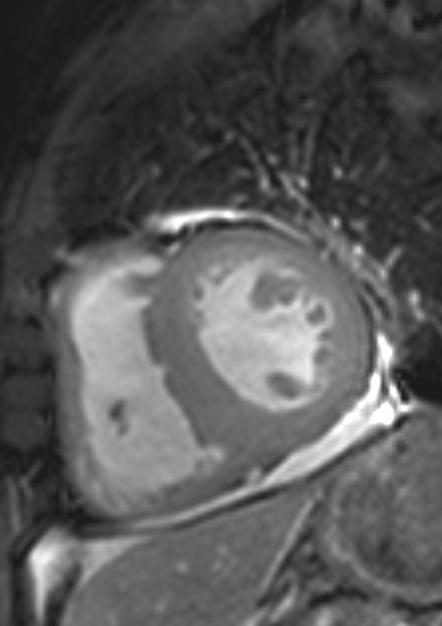

cardiomegaly on x-ray 11/F

Kyungsun Nam, Department of Radiology, Yonsei University College of Medicine

HIT : 16